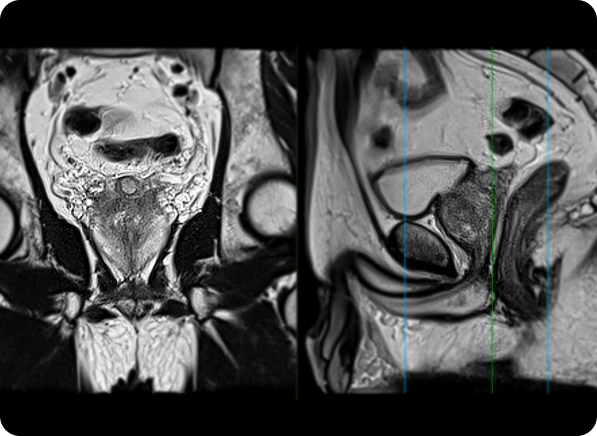

How MRI Technology Improves Precision

MRI provides high-resolution images that reveal detailed prostate structures. By pinpointing suspicious areas with greater accuracy, it minimizes the likelihood of missing clinically significant cancers, leading to more targeted and reliable biopsies.

The Role of Artificial Intelligence in Prostate Imaging

AI algorithms analyze MRI data to highlight abnormalities that could indicate cancer. These tools assist radiologists in interpreting images faster and with increased accuracy, reducing the potential for human error and improving diagnostic confidence.